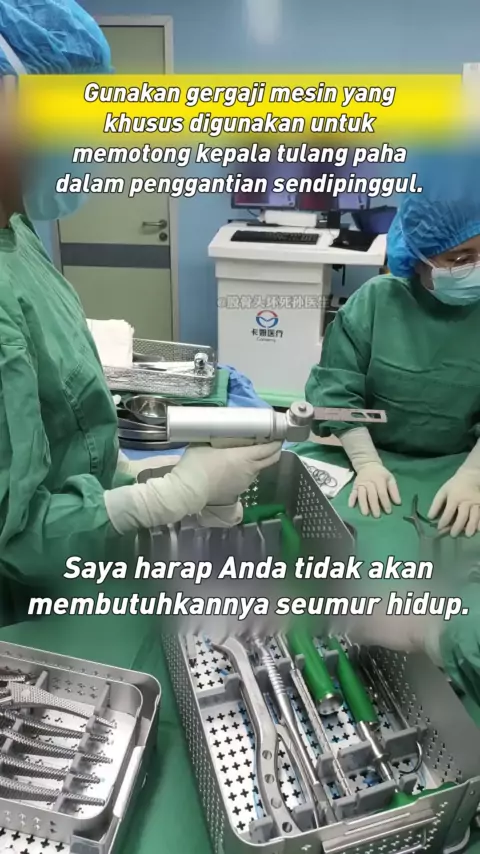

Nekrosis tulang femoralis dan operasi pinggul, seperti yang diharapkan, operasi ortopedi adalah semua kerja keras! # # Hal-hal yang tidak Anda ketahui di ruang operasi # Ruang operasi setiap hari

Sebelum penggantian pinggul buatan, hal-hal yang tidak Anda ketahui tentang # femur bone nekrosis # ruang operasi harian # ruang operasi